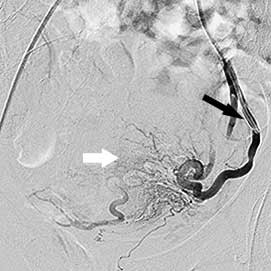

міома матки після емболізації    міома матки після емболізації

Катетер у правій матковій артерії

(чорна стрілка), вузлові артерії

не контрастуються

Катетер у лівій матковій артерії